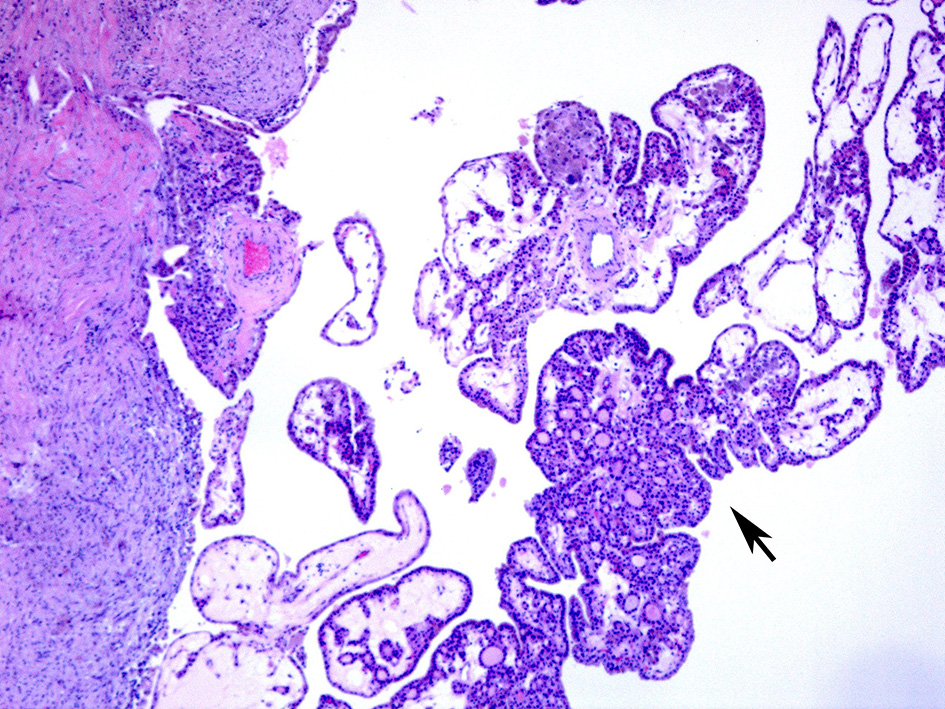

On surgical excision the toxic adenoma grossly shows a distinct capsule and may be centrally cystic. These lesions can also show a papillary pattern of growth without nuclear features of papillary carcinoma. The autonomously functioning nodule usually occurs in young females. This lesion also termed “papillary hyperplastic nodule” (25) (a term coined by the late Dr. Austin Vickery) is an encapsulated or at least circumscribed area in the thyroid composed of exuberant papillary structures often with some follicle formation in the cores of the papillae; the lesions are often centrally cystic and the papillae tend to point toward the center of the nodule. Importantly the nuclei lining these papillary structures are round, have internal structure and are often polarized within the cells (Figures 3, 4). Lymphocytes are rarely found within these lesions (11, 12). Most of these nodules are clonal proliferations and are therefore considered adenomas (26–29). (The term “papillary adenoma” would be an appropriate one for these lesions; however, this term is shunned since it has been used to described encapsulated papillary carcinomas in older literature) (30). Although the great majority of these hyperplastic nodules are not associated with clinical hyperthyroidism, about 15–20% of affected patients do have symptomatic hyperfunction and about another 30% have biochemical hyperthyroid indices (25, 31, 32).

Figure 3. A case of papillary hyperplastic nodule on low power showing cystic nodule with papillary architecture (arrow).